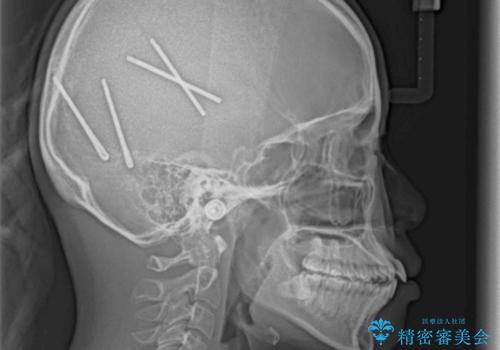

短期間で口元の突出感を改善 ワイヤー装置での抜歯矯正

- 口元の閉じにくさを気にして来院された患者様です。

上下ともに歯列が前方に突出していたため、上下左右の第一小臼歯4本を抜去し、ワイヤー装置による矯正治療を行うこととしました。

舌の突出癖による影響もあったため、舌のトレーニングを並行して実施しました。